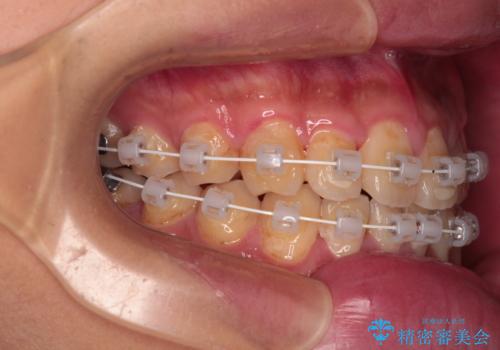

クロスバイトはありましたが、叢生の程度としては酷くなかったため、ワイヤー矯正でもマウスピース矯正でも、好きな方を選択していただきました。

一日中マウスピースを装着する煩わしさから、マウスピース矯正を継続する自信がないとのことで、ワイヤー装置にて矯正治療を行うこととしました。